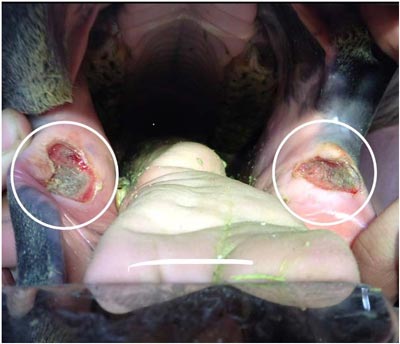

Abnormalities in the soft tissue of the mouth or very sharp points on the teeth will cause a horse increased discomfort with bit contact or pressure from cheek pieces. For these reasons it is the examination that is more valuable then simply the dental / tooth floating.

If sharp enamel points are present they can be rasped away by hand or motorized tools, this will reduce the chance of the cheeks or tongue being traumatized by these sharp areas.